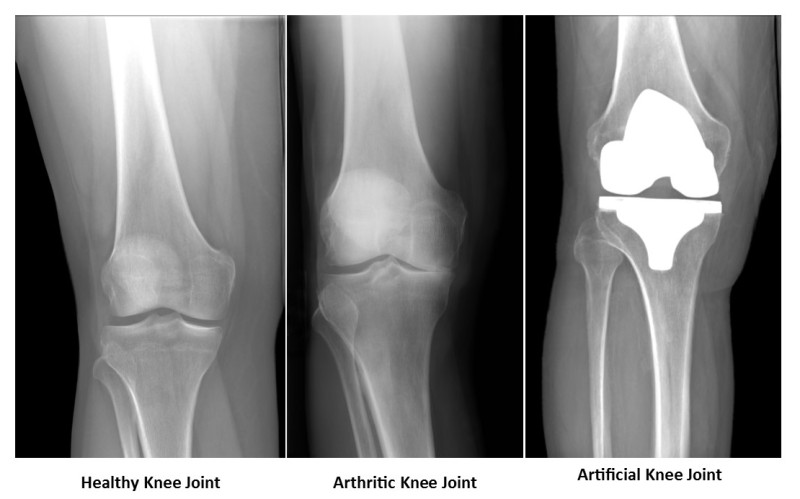

The knee functions as a hinge joint. The joint is made from the end of the thigh bone (femur), where it meets the shin bone (tibia) and the knee cap (patella). Normally, the cartilage coating over the bones makes the joint move smoothly and provides an additional shock-absorbent cushion. In an arthritic knee, the cartilage surface wears out and begins rubbing bone on bone which causes pain, stiffness, and swelling of the knee joint.

In a total knee replacement surgery, the arthritic surfaces of the knee joint are removed and new surfaces are provided with metal and poly (plastic) parts. This relieves knee pain and allows the joint to move smoothly again.